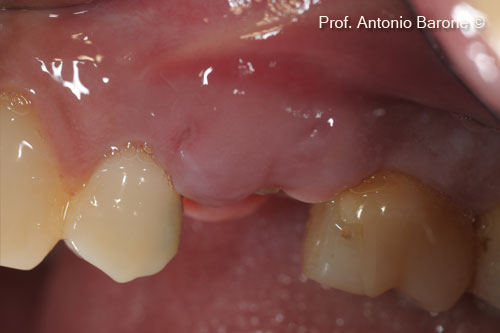

Hình ảnh lâm sàng của một ổ răng mới bị mất hoàn toàn xương nền má

Hình ảnh lâm sàng mặt nhai cho thấy quá trình lành thương sau 2 tháng

Hình ảnh lâm sàng mặt nhai cho thấy quá trình lành thương sau 5 tháng

Hình ảnh lâm sàng của sống hàm sau 5 tháng lành thương. Mẫu sinh thiết xương đã được lấy